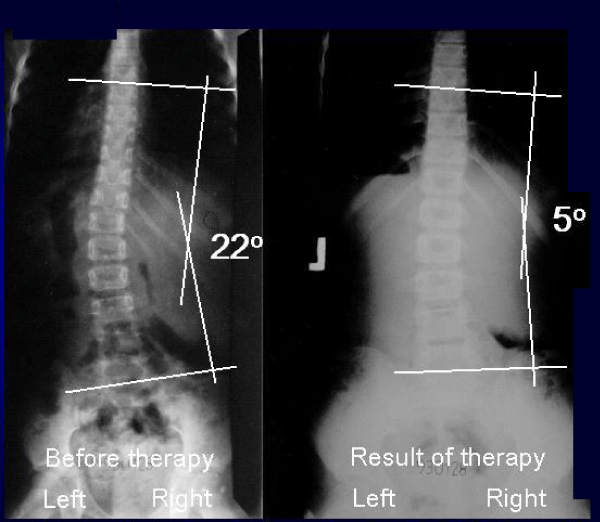

图8:孩子Weronika, 10岁。930128年的历史。脊柱侧凸“C”在2nd/epg组和类型。4年新疗法。在项目中:(1)仅在左腿上“轻松地”站立,(2)每天多次向前和向左弯曲练习,(3)学校运动,空手道,(4)右侧胚胎姿势休息和睡觉。